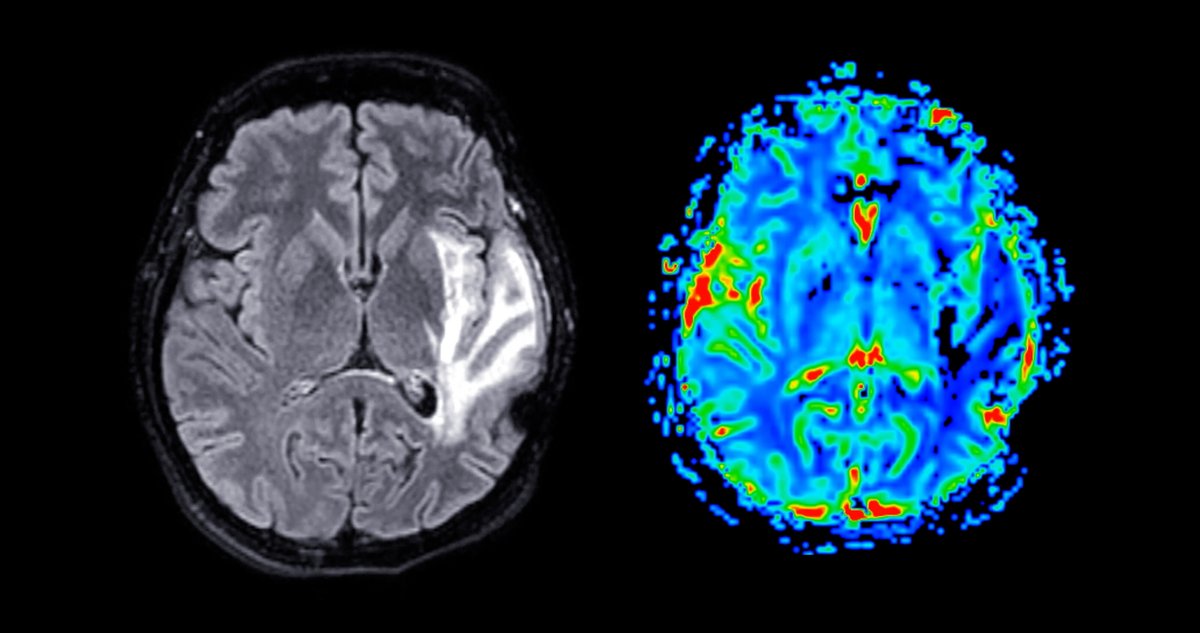

Магнитно-резонансная томография (МРТ) – это один из безопасных, неинвазивных (т.е. без нарушения целостности кожных покровов), высокоточных методов исследования органов. В основе метода лежит явление ядерно-магнитного резонанса, то есть способности атомов водорода менять свои свойства и положение под воздействием электромагнитных волн разной направленности в постоянном магнитном поле. При этом считывающий датчик улавливает эти изменения, а специальная программа преобразует их и выводит на экран монитора в виде изображения.

Разные типы тканей имеют свою плотность атомов водорода. Когда в них появляются изменения (например, формируются опухолевые клетки или гибнут здоровые), то они приобретают другие свойства, меняются и их резонансные характеристики.  Все эти отклонения будут зафиксированы томографом и выведены на экран монитора.

Для некоторых состояний достаточно нативного (обзорного) исследования, для других – дополнительно требуется применение контрастного вещества, изменения со стороны сосудистого русла выявляют с помощью режима ангиографии.

Полученные снимки изучает специалист по магнитно-резонансной томографии. Он описывает здоровые ткани и все выявленные изменения, указывая их расположение, размеры, изменение плотности, границы. В отношении патологии сосудов головного мозга и шеи указывается наличие аневризм, мальформаций, гипоплазии, аномалий развития, стенозов с их протяженностью, локализацией и степенью сужения просвета сосуда, зоны с усилением или ослаблением кровотока, тромбозов и окклюзий.